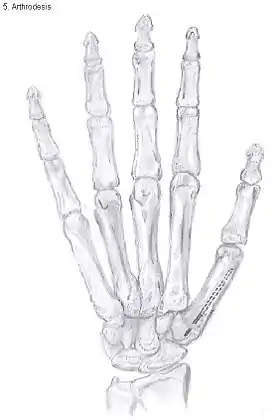

Arthrodesis

Arthrodesis of the TMC joint is a surgical procedure in which the trapezium bone and the metacarpal bone of the thumb are secured together. They are held together by K-wires or a plate and screws until the bone will heal.

Disadvantages include inability to flatten the hand.[27] Additionally, the stress on the CMC joint is now spread over the adjacent joints, those joints are more likely to develop osteoarthritis.[34]

Nevertheless, this procedure can be used in patients with stage II and III CMC OA as well as in young people with posttraumatic osteoarthritis.[27]